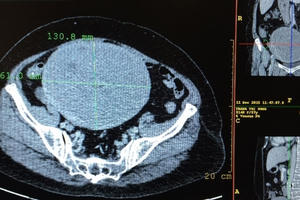

Bệnh nhân 38 tuổi (Phú Thọ) được các bác sĩ khoa Sản Bệnh viện Đa khoa Hùng Vương phẫu thuật cắt khối u xơ tử cung nặng gần 2 kg.

Khối u của bà H, 58 tuổi, Bắc Cạn có kích cỡ lớn, chiếm gần hết phần tử cung và gây nguy hiểm đến tính mạng. Nhưng rất may, khối u này đã được phẫu thuật thành công.